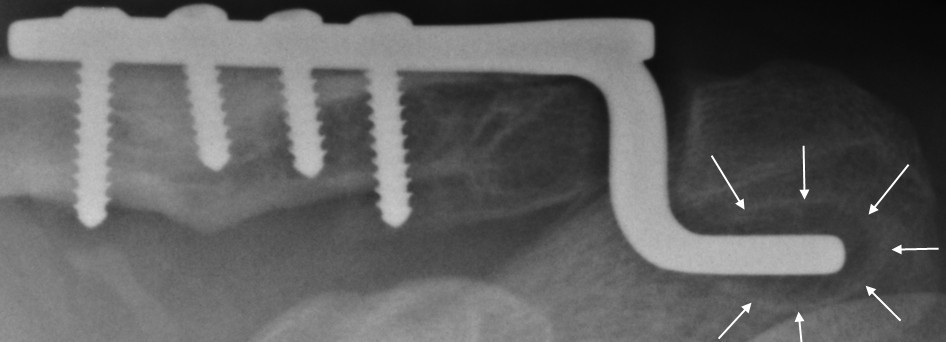

There are many surgical options for the treatment of type v ac separation, and each has pros and cons. Surgical fixation can involve the use of a hook plate which is placed under the acromion bone and levers the displaced clavicle down. [ 12 ] found that the placement of the clavicular hook plate would inevitably narrow the subacromial clearance, which may be related to the occurrence of sis.

Hook plate fixation generally requires a second surgery for plate removal, but it allows for firm fixation and early shoulder mobility. The surgery was successfully completed without A superior approach to the ac joint was used, and the hook of the hook plate and a reduction clamp were used to achieve reduction.

The clavicle hook plate provides a single solution for fixation of both lateral clavicle fractures and acromioclavicular joint injuries. The major disadvantages of hook plate cited in earlier series have been repeat surgery, persistent shoulder pain, incomplete shoulder function, acromial osteolysis and acromioclavicular subluxation. The pain after surgery needs to be controlled on oral medications before discharge.

Open reduction and internal fixation of the coracoid fragment can be performed depending on the displacement and size of the distal fragment. Several studies [2, 9, 11] have shown that older patients who underwent hook plate surgery have increased risk of sis, which may be related to shoulder tissue degeneration. The hook of the plate runs behind the ac joint and holds the shoulder blade up to the collarbone.